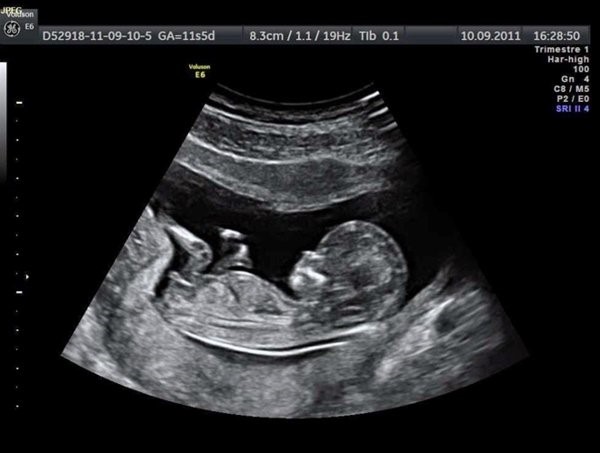

Siêu âm thai 5 tuần bác sĩ và mẹ sẽ thấy gì?

Điều thắc mắc lớn nhất của nhiều chị em khi thực hiện siêu âm thai 5 tuần tuổi đó là mẹ sẽ thấy gì. Tuy hình ảnh qua các thiết bị có thể không rõ nét nhưng một số thay đổi đã bắt đầu xuất hiện trên phôi thai mà bác sĩ có thể thấy được như:

– Phôi thai và tim thai: Ở một số bà mẹ có phôi thai phát triển nhanh thì đã có thể thấy được tim thai khi siêu âm thai 5 tuần tuổi.

– Túi noãn hoàng: Khi siêu âm vào giai đoạn này thì có thể bác sĩ sẽ thấy được túi noãn hoàng của thai.

– Túi thai: Túi thai là bộ phận có chức năng bao bọc thai nhi và nước ối. Vì thế khi siêu âm thai 5 tuần tuổi, mẹ sẽ có thể nhìn thấy được túi thai một cách rõ nét.